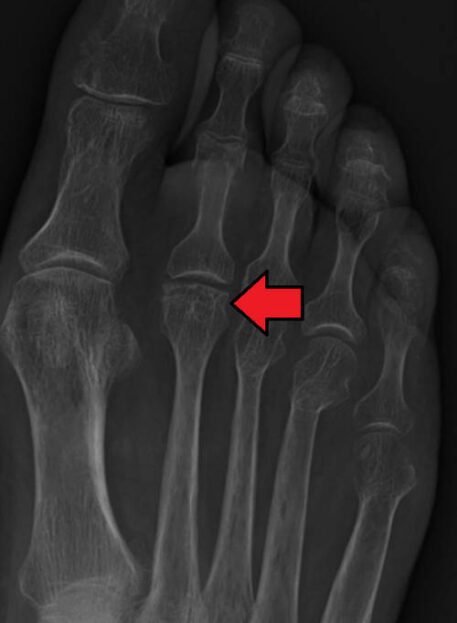

Hallux rigidus je degenerativna oblika artritisa prvega metatarzofalangealnega (MTP) sklepa, pri katerem pride do zmanjšane gibljivosti palca in bolečin na zgornji strani stopala. Pogosto prizadene starejšo populacijo, vendar se lahko pojavi tudi pri mlajših ljudeh – zlasti po poškodbah ali zaradi biomehanskih sprememb stopala.

Deformacija nožnega palca-Hallux valgus

Poznamo tri oblike:

- Metatarzalna kost pomaknjena navznoter, prva falanga v normalni legi

- Metatarzalna kost normalno, prva falanga pomaknjena navzven

- Najpogostejša: metatarzalna kost navznoter, prva falanga navzven